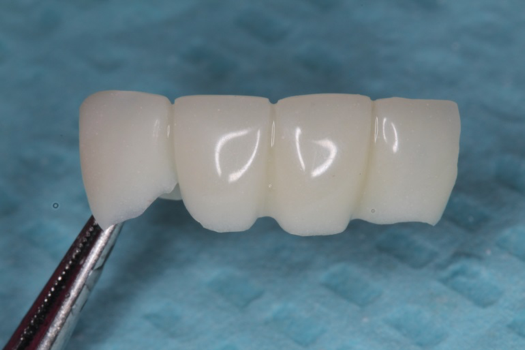

Fig 43. PMMA provisional digitally fabricated and milled.

Figure 43

On the day of surgery, the plan was to extract teeth Nos. 21, 23, 24, 25, and 26, place 3.0 x 13-mm implants in the anterior region due to limited spacing, and place a 4.1 x 10-mm implant in the No. 21 extraction site. Before the extractions were performed, the No. 23 pontic was sectioned from the existing 2-unit cantilevered bridge utilizing ceramic and metal high speed rotary cutting burs ZR 6881 and H34L (Komet-USA), respectively. After removal of the pontic and extractions, the surgical guide was verified to be seating positively (Figure 36 through Figure 38). Surgical guide protocol was followed, and all implants were successfully placed and torqued to a value of greater than 35 Ncm (Figure 39 and Figure 40). All implants were placed without flapping, with the exception of No. 23. The flap was elevated to reposition lingual keratinized tissue facially for enhanced esthetic tissue profile. The implants were then prepared with a high-speed carbide bur (Komet-USA) with copious amounts of water (Figure 41 and Figure 42). The one-piece 3.0-mm diameter implant served the needs of the patient's spacing requirements. Inter-occlusal space requirements and path of draw were verified. The PMMA provisionals were air abraded and relined with crown-and-bridge material (Figure 43 through Figure 45).

Due to the guided surgical and prosthetic protocol, this case was completed with tissue sparing and atraumatic extractions with precision implant placement. The most arduous task of the entire procedure was the physical implant abutment preparation for proper clearance. If the patient had more space to plan her treatment, implants using a two-piece protocol would have been implemented with screw-retained non-engaging provisionals after implant placement. Again, this decision process is solely in the hands of the clinician providing services.